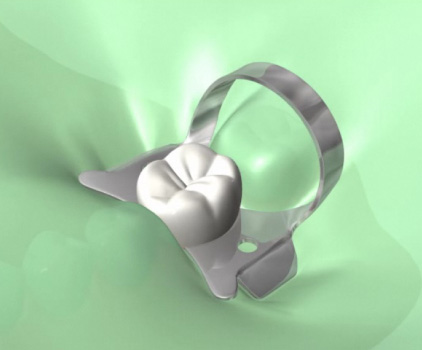

ラバーダム防湿について

お口の中はばい菌だらけです。根の治療をするにあたり根の中にばい菌をできるだけ入れないように配慮が必要です。

金属の金具とゴムのマスクを使ってばい菌の侵入を最小限にするのがラバーダム防湿です。

日本ではあまりなじみのない方法ですが、質の高い歯科治療には必要になります。

なぜラバーダムが必要か?

■根管治療の成功率

ラバーダム(ゴムのマスク)を使用した場合:約90%(初回治療時)

ラバーダム(ゴムのマスク)を使用しない場合:約50%以下(初回治療時)

※初回治療時にラバーダムを使用した場合の、再治療時の成功率は約60%。

ラバーダムの使用により治療の予後が向上します。